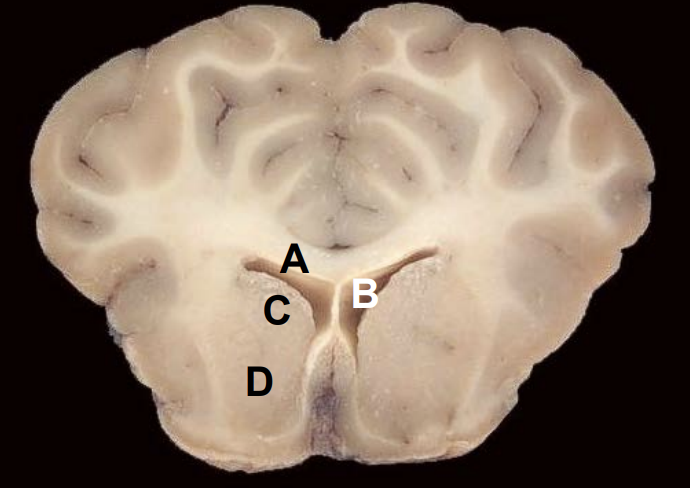

1

Q

A

Corpus callosum

B

Lateral ventricle

3

C

Caudate nucleus

4

D

Putamen